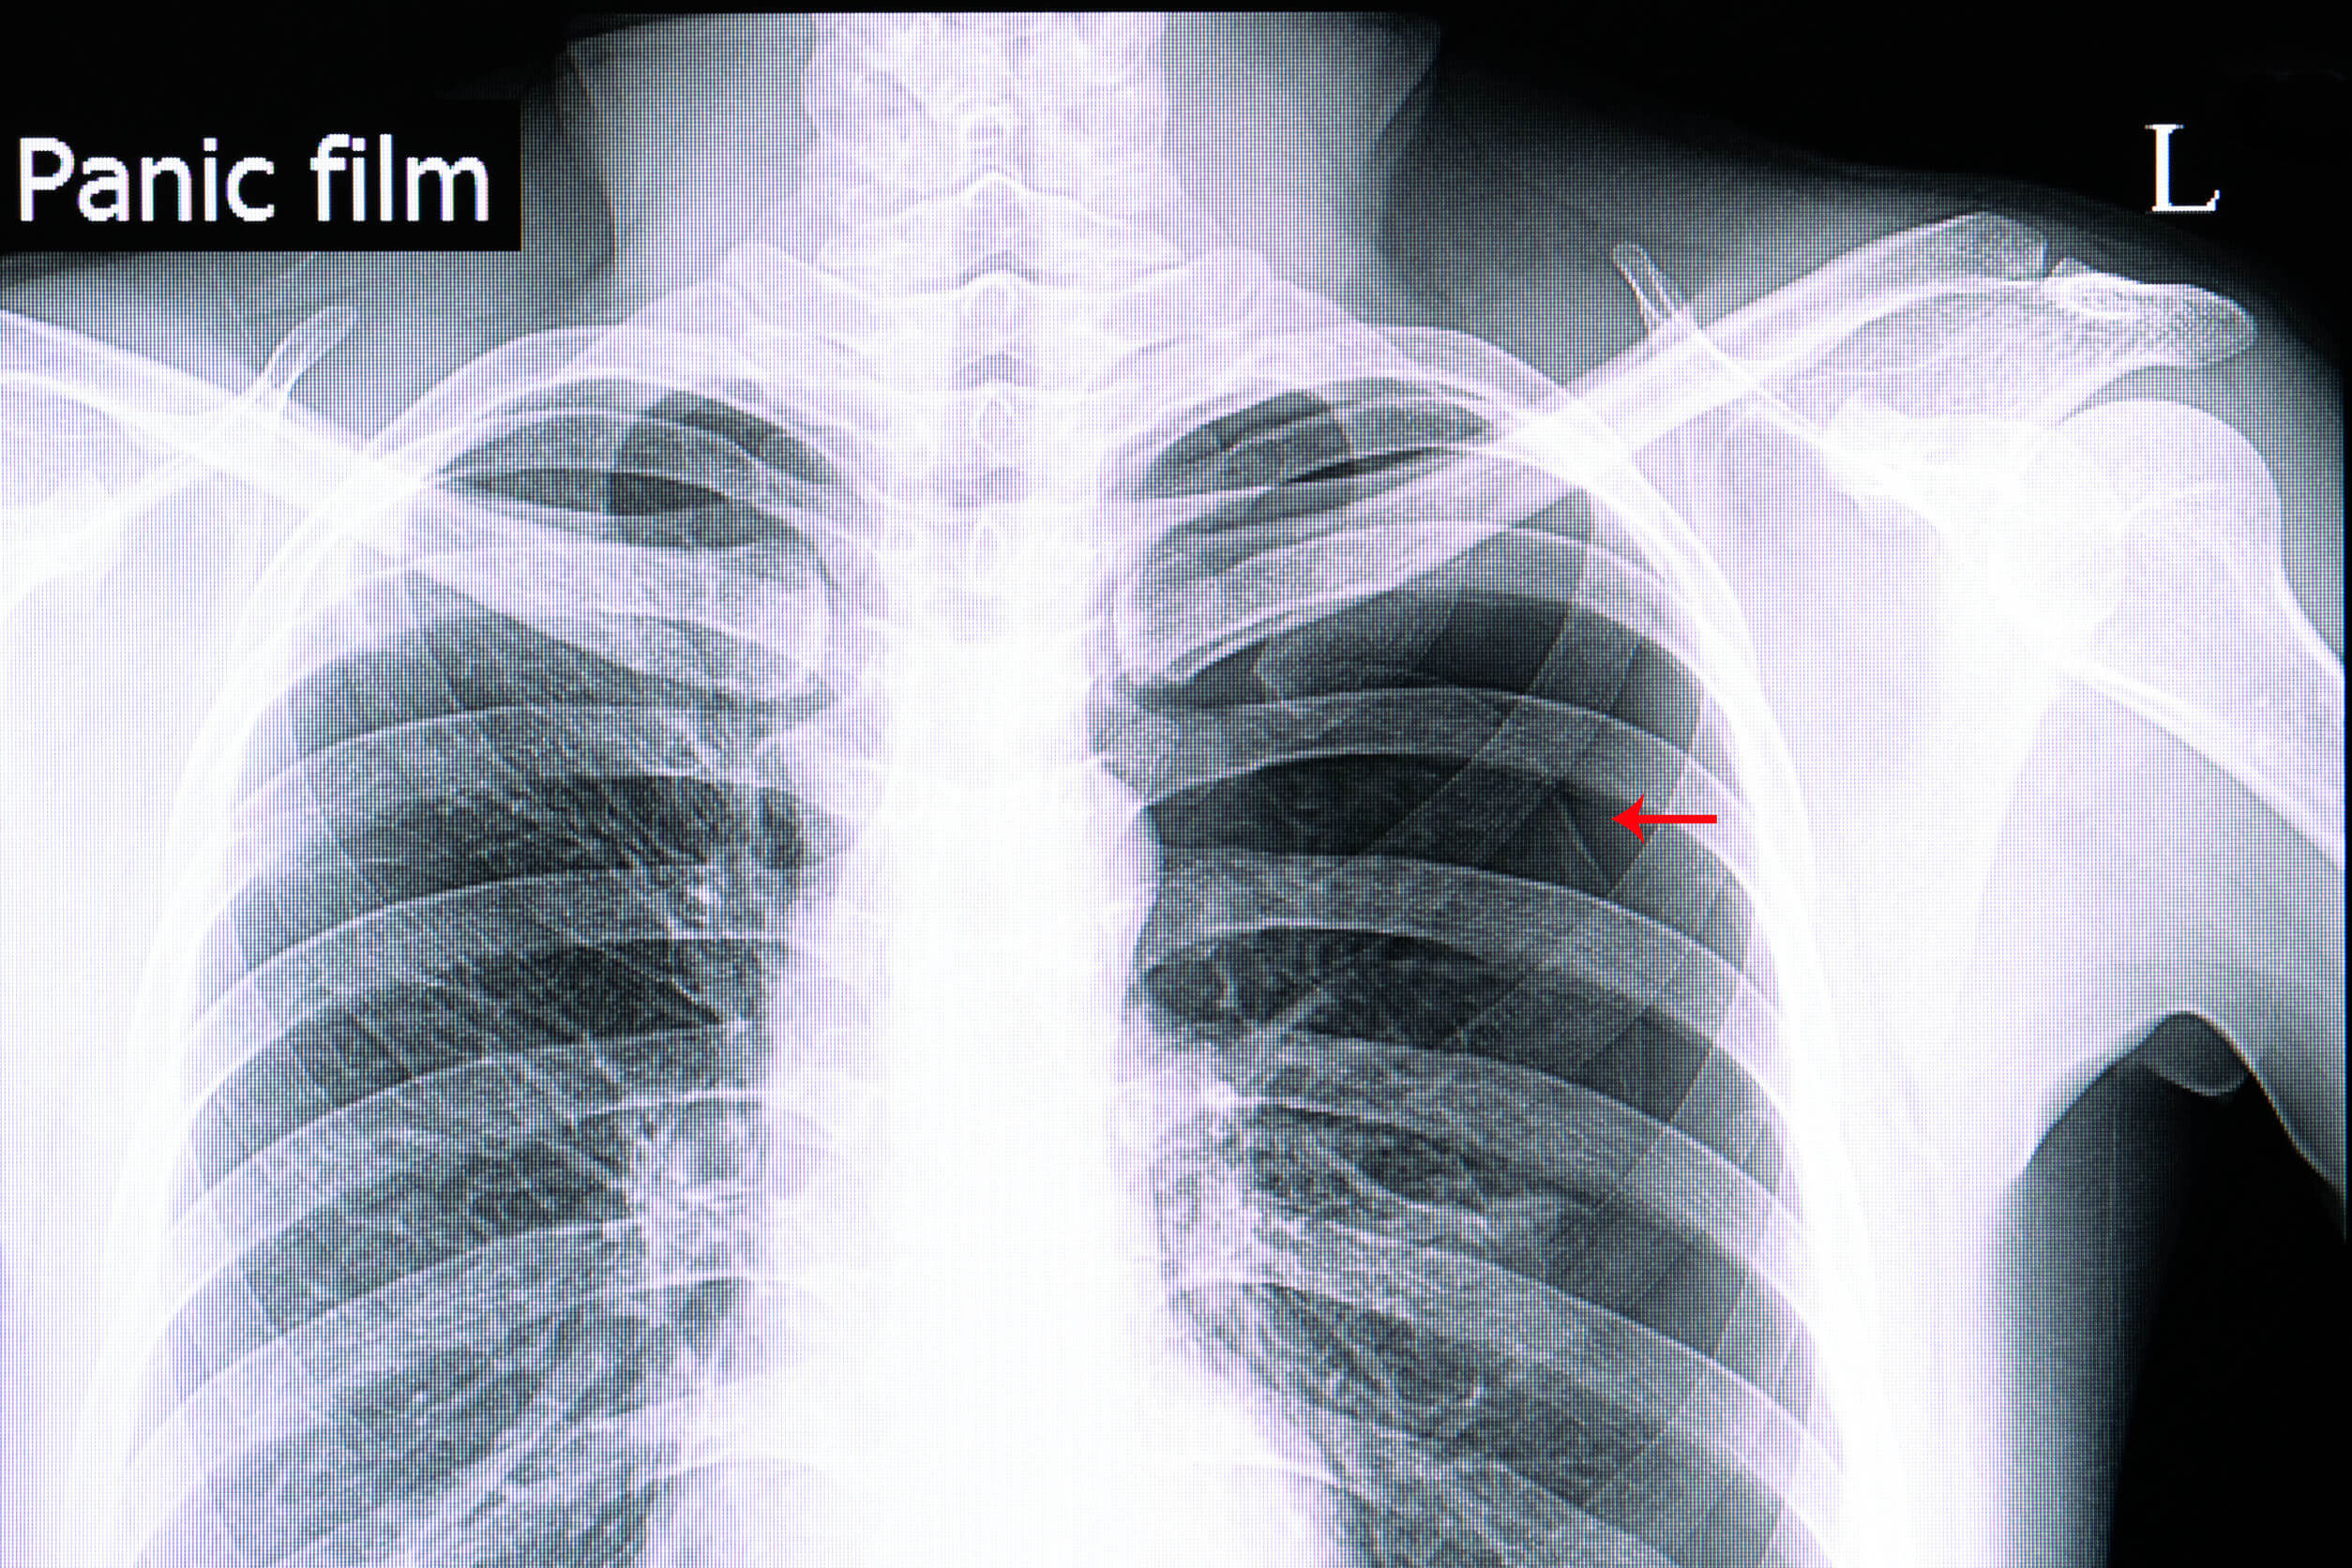

Diagnosi di pneumotorace

La diagnosi è per lo più clinica; si può ricorrere a esami complementari nei casi in cui la vita del paziente non sia a rischio immediato.

Tra questi, la radiografia del torace è la più indicata. Il collasso del polmone e delle sue strutture vascolari è solitamente molto evidente, nonostante in alcuni pazienti possa passare inosservato. In quest’ultimo caso, può essere utile ricorrere a una scansione TC.